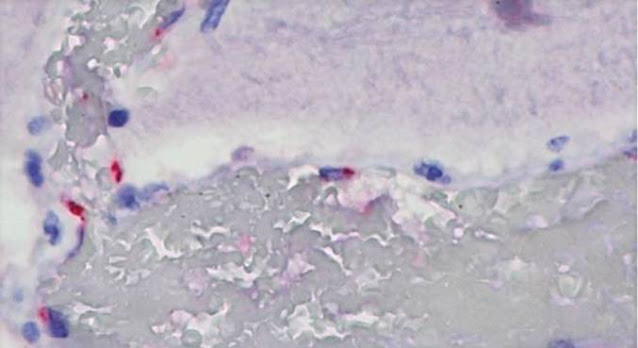

A presença do SARS-CoV-2 nos tecidos foi determinada por reação em cadeia da polimerase por transcrição reversa (RT-PCR, o mesmo teste usado no diagnóstico da COVID-19) e por imuno-histoquímica, método em que são usados anticorpos capazes de detectar duas proteínas do vírus: a N, do nucleocapsídeo, e a S2, dos “espinhos” (spikes) da superfície viral.

O novo coronavírus foi detectado em células endoteliais e musculares do coração no paciente com miocardite, no tecido intestinal da criança com colite aguda e no tecido cerebral da que desenvolveu encefalopatia aguda.

Os pesquisadores observaram que um dos principais alvos do novo coronavírus são as células endoteliais, que revestem a parede interna dos vasos, incluindo desde as artérias de grande calibre até os capilares sanguíneos mais delgados.

“Uma das hipóteses é que, ao ser infectada, a célula endotelial dispara mediadores na corrente sanguínea que provocam uma cascata de inflamação que causa toda essa reação observada em crianças com a SIM-P, como febre persistente, colite, miocardite e encefalite”, explica Amaro Nunes Duarte Neto, infectologista e patologista da FM-USP e do Instituto Adolfo Lutz e um dos primeiros autores do estudo.

Análises feitas por microscopia eletrônica pela professora da FM-USP Elia Caldini sustentam essas conclusões.

A técnica permite o reconhecimento direto da partícula viral, com aumento de mais de 50 mil vezes, sem a utilização de reações específicas. Dessa forma, foi possível descrever as alterações citoplasmáticas nas células associadas à presença do vírus

“Em busca de um método inequívoco de identificação, também empregamos, de maneira inédita, a técnica de imunomarcação do SARS-CoV-2 na microscopia eletrônica. Usamos partículas de ouro coloidal acopladas aos mesmos anticorpos específicos usados na microscopia de luz contra proteínas estruturais do SARS-CoV-2”, explica Caldini.